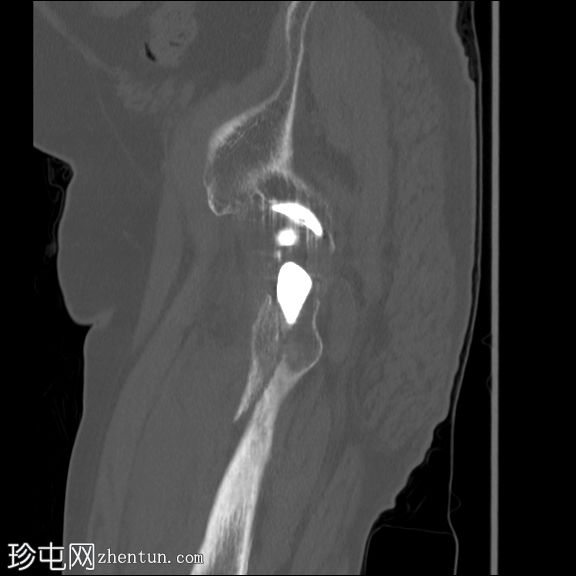

矢状骨窗

冠状骨窗

左股骨内存在轻微移位的假体周围骨折。

左大腿前部可见大量肌肉,可能提示血肿。但未见明显可引流积液。